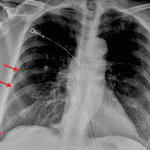

Age: 71

Sex: Female

Indication: Shortness of breath

Case #33

Findings

- Thin curvilinear density along the lateral aspect of the right hemithorax

- Mild streaky bibasilar opacities

- No pleural effusion

- Normal size and configuration of the cardiopericardial silhouette

Diagnosis

- Loculated pneumothorax

Sample Report

Sample Report

Thin curvilinear density along the lateral aspect of the right hemithorax which may represent a pneumothorax versus external artifact. Recommend right-side-up decubitus radiographs or CT for further evaluation.

Mild bibasilar atelectasis.